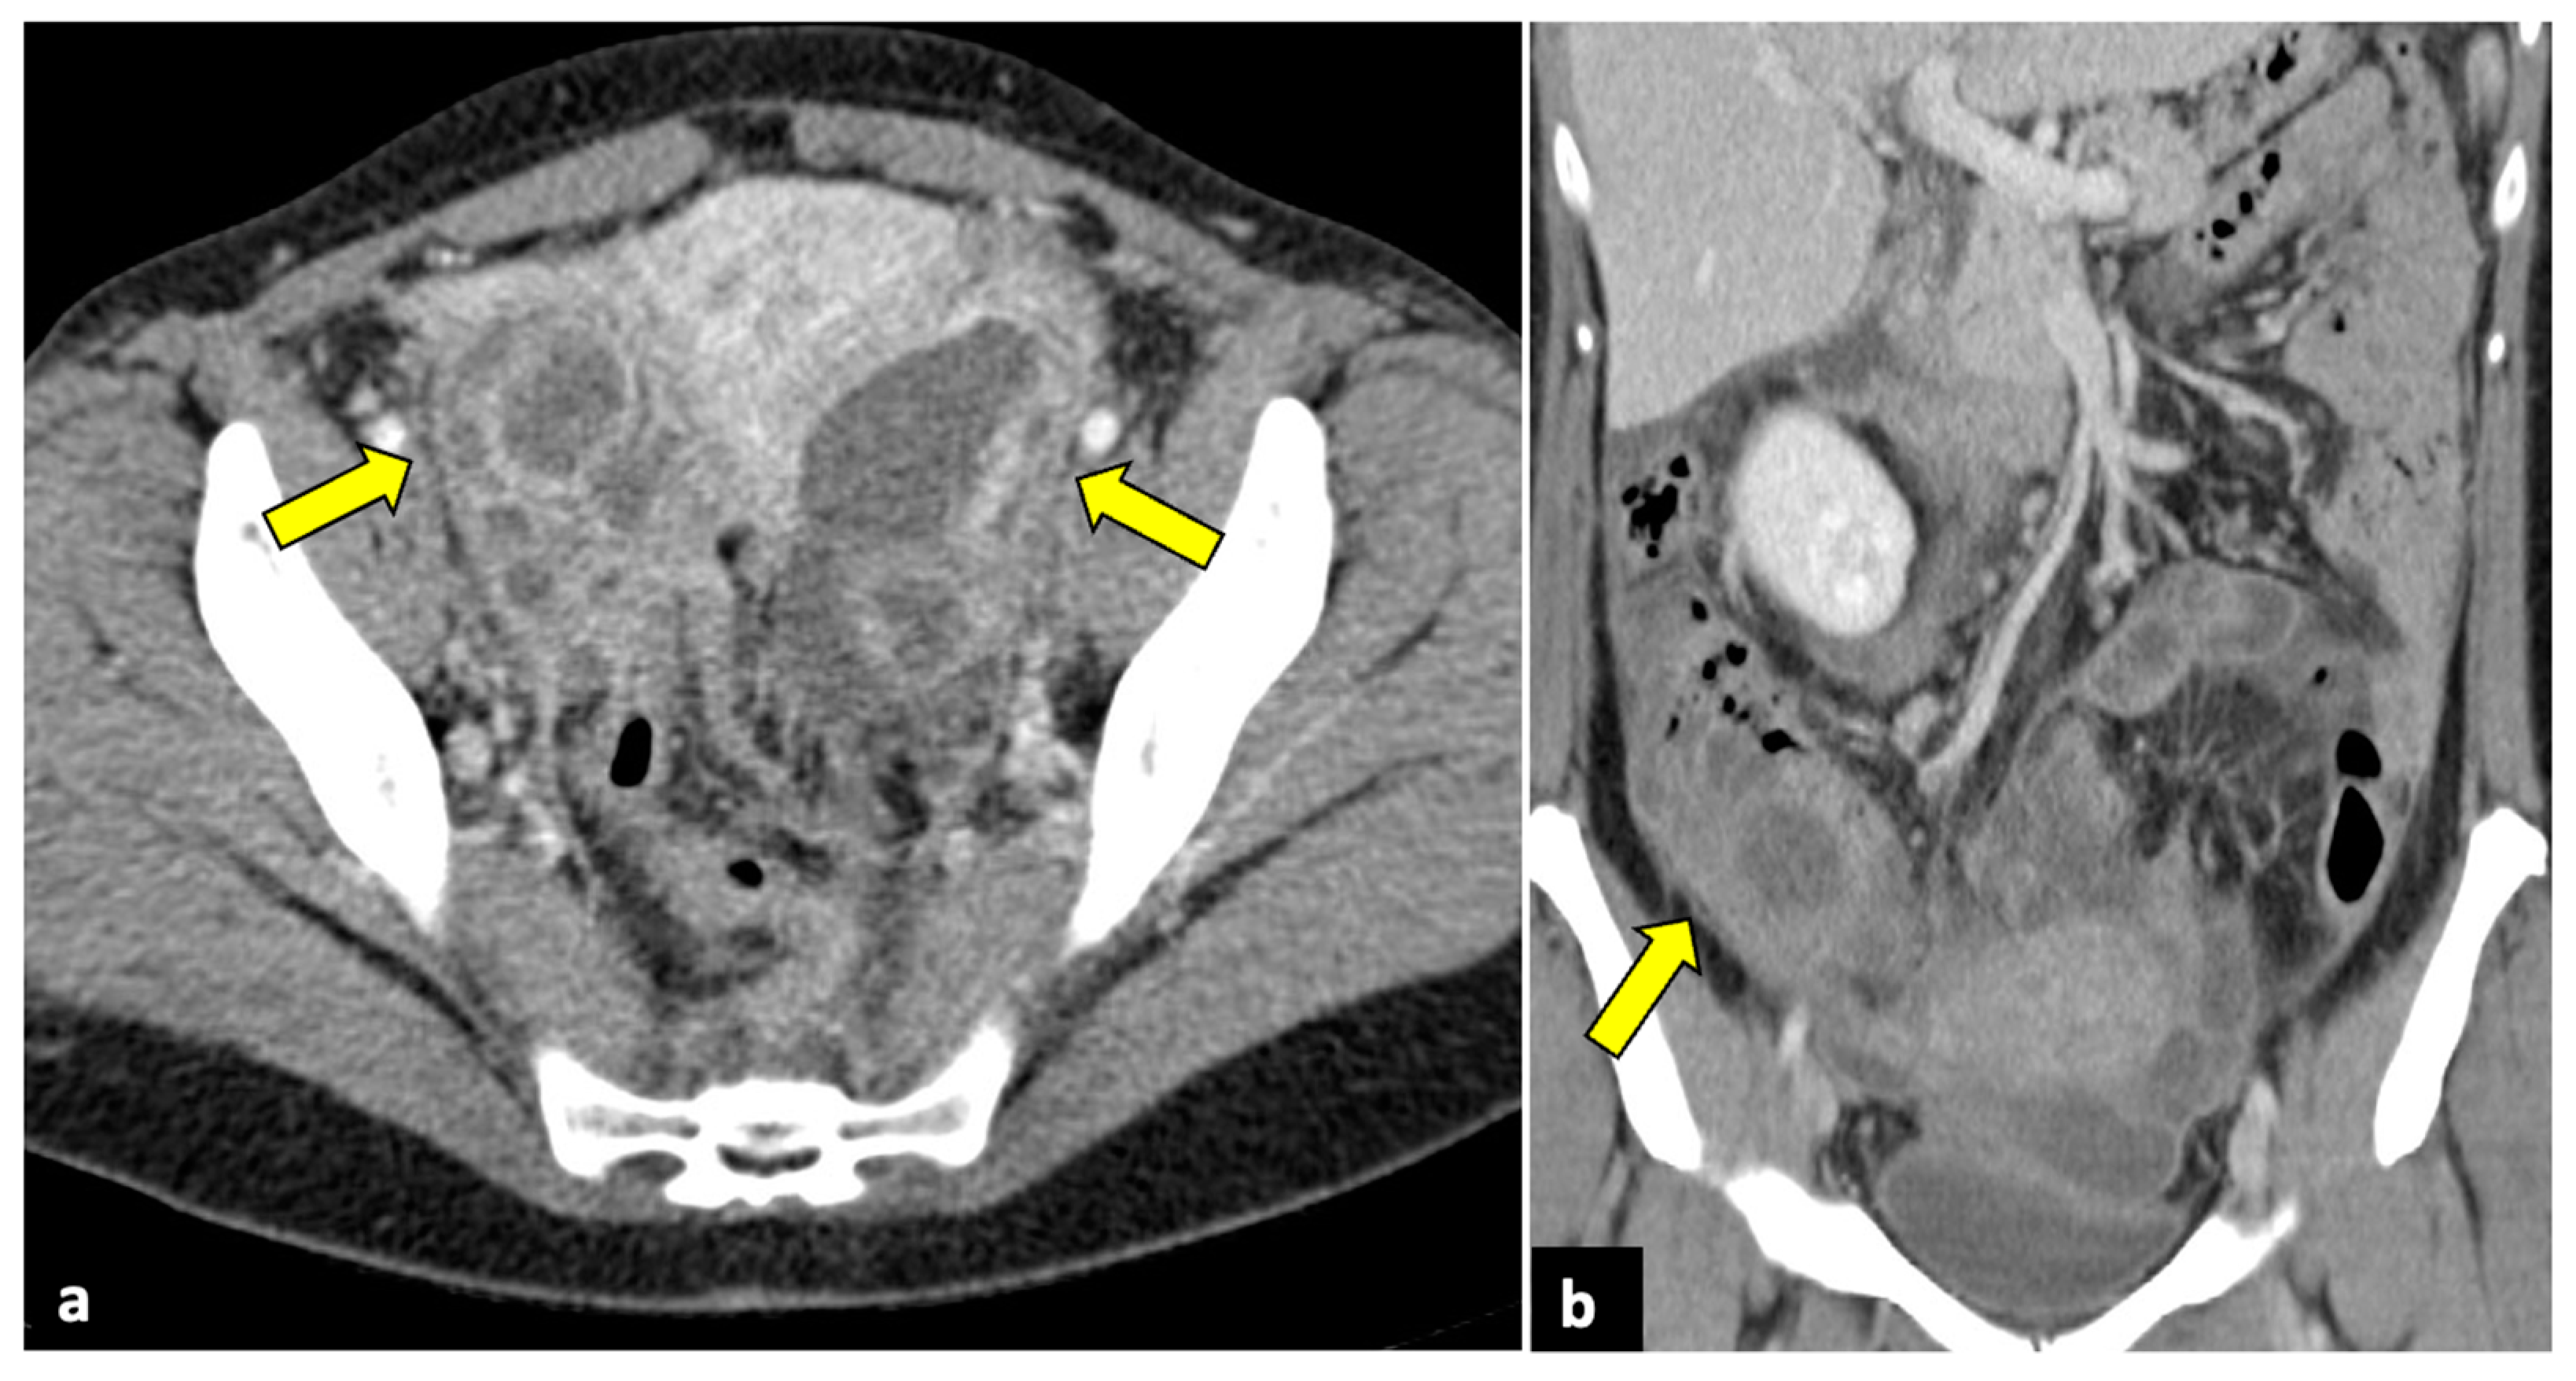

Figure 10.

Advanced uterine cervical cancer in a 58-year-old subject attending the emergency department for abdominal pain and haematuria. CT axial (a), sagittal (b), and coronal (c) non-contrast images reveal the presence of a pelvic mass (blue arrows) and ureter causing ureteral obstruction (yellow arrows). The patient further underwent an MRI examination (d–f), which demonstrated a cervical tumour (blue arrows) invading the parametrium and ureters bilaterally (yellow arrows), the vagina, and the bladder. The uterine cavity was also obstructed and dilatated (red arrows).